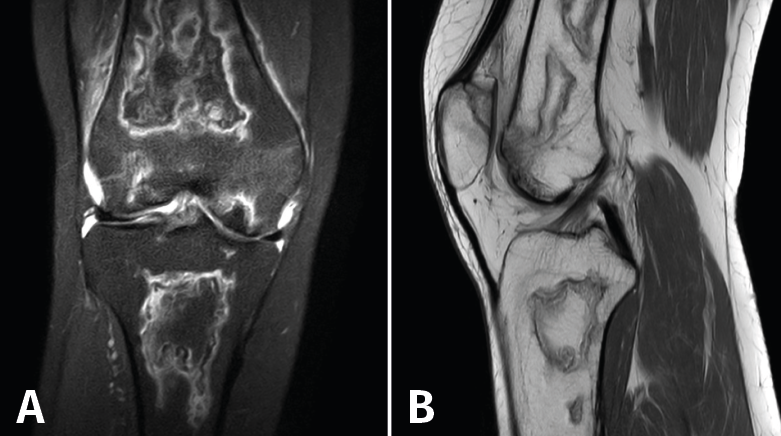

4.2. Infartos

Los infartos medulares óseos aparecen en el 0,06% de los pacientes a quienes se les ha realizado una RM del aparato locomotor. Se presentan como lesiones segmentarias, puramente medulares, sin afección cortical, normalmente múltiples y que afectan predominantemente a los huesos largos de las extremidades, sobre todo las inferiores. La RM es esencial en el diagnóstico por imagen, apareciendo como lesiones óseas intramedulares de contornos serpiginosos hipo- o isointensos en secuencias T1 e hiperintensos en T2. Por tanto, la RM es el instrumento crucial en las fases iniciales, ya que permite caracterizar las lesiones y proceder a su diagnóstico temprano(19)(Figura 52).

Figura 52. A: corte de secuencia coronal T2 Fat-Sat con infartos óseos en el fémur y la tibia; B: corte de secuencia sagital T1 con infartos óseos en el fémur y la tibia.